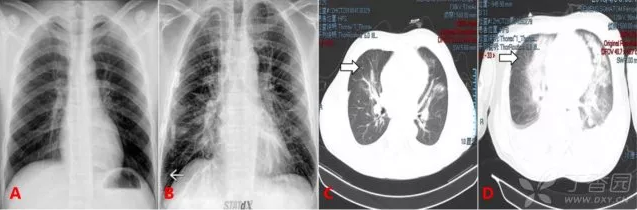

QQ瀏覽器截圖20200505212739.png

圖 6 心源性肺水腫典型表現(xiàn):蝶形影/蝙蝠翼樣表現(xiàn)

圖 6A 顯示的是肺水腫患者的普通胸片,可見雙肺紋理明顯增多,以肺門為中心的彌漫性滲出影。近胸膜處不明顯,即蝶形滲出,中心大于外周。

圖 6B 為肺水腫患者的 CT 顯像,同樣表現(xiàn)為中心大于外周的彌漫滲出,稱之為蝙蝠翼征。

圖 6C 可見雙肺彌漫廣泛滲出,但近胸膜處滲出影明顯多于肺門周圍,即外周大于中心,該片為過量使用可卡因?qū)е录毙苑嗡[。